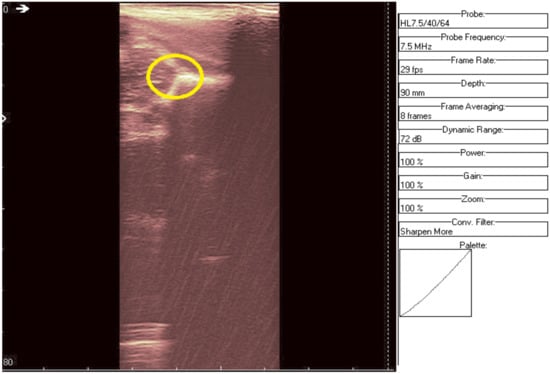

We can remark, when analyzing the zoomed parts of Figure 4 and Figure 5 (the acetabulum), that in the original image speckle noise appears, strongly affecting the image. The filtering system proposed in this paper does not completely remove the speckle but brightens the image, at the same time not oversmoothing the original image. The main bone structure can be better outlined. A comparison between the same zoomed region of interest in the original image and denoising result, showing the disappearance of the speckle grains (Figure 6)—resulting thus in a smoother image where anatomical features can be better outlined.

Figure 5. Same region of interest as in Figure 4 was encircled in yellow. The interior speckle grains have disappeared.